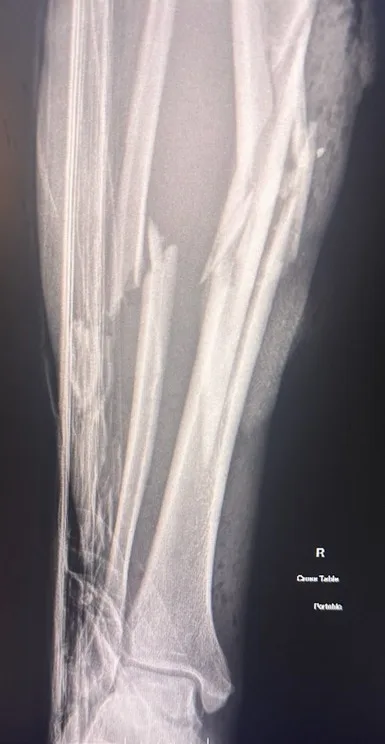

I was rushed in for X-rays and blood tests but minutes later the doctor returned.

I was rushed in for emergency surgery, where a titanium rod was inserted to save my leg. I also received a blood transfusion.